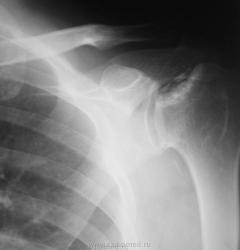

Пол пациента: Мужской пол Тип патологии: Другое Область исследования: Скелетно-мышечная система Методы исследования: Rg Мужчина пожилого возраста обратился с жалобами на боль при движении левой рукой, особенно при отведении её в сторону и вверх. https://radiomed.ru/sites/default/files/styles/case_slider_image/public/user/12/01.1..sl272871.jpg?itok=oY80RVfp https://radiomed.ru/sites/default/files/styles/case_slider_image/public/user/12/02.2..sl272871-3a.jpg?itok=myiw2wOv ID:5598 Ср, 18/08/2010 - 21:18 #1 Катенёв Валенти... Не на сайте Был на сайте: 7 лет 5 месяцев назад Зарегистрирован: 22.03.2008 - 22:15 Публикации: 54876 Здравствуйте Игорь Артурович! Интересный случай представлен Вами. Приложения: Ср, 18/08/2010 - 21:20 #2 Катенёв Валенти... Не на сайте Был на сайте: 7 лет 5 месяцев назад Зарегистрирован: 22.03.2008 - 22:15 Публикации: 54876 Продолжение. Приложения: Ср, 18/08/2010 - 21:20 #3 Глазков Игорь А... Не на сайте Был на сайте: 1 год 2 месяцев назад Зарегистрирован: 19.12.2008 - 20:41 Публикации: 1597 что здесь не только банальный артроз, но больше похоже на сирингомиелию? Прийди к Себе Ср, 18/08/2010 - 21:37 #4 Almo Не на сайте Был на сайте: 3 недели 19 часов назад Зарегистрирован: 28.09.2008 - 18:50 Публикации: 8302 Артроз есть. Сирингомиелия?( должны быть симптомы выпадения темературной чувствителности на руке) Я бы, предложил версию асептического некроза головаки плеча. Ср, 18/08/2010 - 21:40 #5 Глазков Игорь А... Не на сайте Был на сайте: 1 год 2 месяцев назад Зарегистрирован: 19.12.2008 - 20:41 Публикации: 1597 за высказанное мнение. Прийди к Себе Чт, 19/08/2010 - 06:54 #6 Анатолий Владим... Не на сайте Был на сайте: 8 лет 3 месяцев назад Зарегистрирован: 16.10.2009 - 21:16 Публикации: 1941 Согласен с мнением Almo, считаю, что здесь - асептический некроз. Чт, 19/08/2010 - 08:12 #7 Широков.Евгений. Не на сайте Был на сайте: 11 лет 8 месяцев назад Зарегистрирован: 31.08.2008 - 14:29 Публикации: 77 Отдаю свой голос за асептический некроз. Чт, 19/08/2010 - 09:33 #8 Грицько Виталий Не на сайте Был на сайте: 9 лет 4 месяцев назад Зарегистрирован: 05.01.2010 - 14:06 Публикации: 1058 Опоздал на все обсуждения:( согласен с асептическим некрозом. Чт, 19/08/2010 - 12:32 #9 Катенёв Валенти... Не на сайте Был на сайте: 7 лет 5 месяцев назад Зарегистрирован: 22.03.2008 - 22:15 Публикации: 54876 Надо признать, что наблюдение, представленное Вами, уважаемый Игорь Артурович, довольно редкое и займет достойное место в наборе "Асептический некроз" Чт, 19/08/2010 - 16:12 #10 Helios Не на сайте Был на сайте: 1 год 2 недели назад Зарегистрирован: 06.08.2010 - 15:16 Публикации: 4417 Голосую за асептический некроз. Чт, 19/08/2010 - 17:03 #11 lupan Не на сайте Был на сайте: 7 лет 3 месяцев назад Зарегистрирован: 07.01.2010 - 17:17 Публикации: 1406 А есть название по автору? Великое преймущество врача заключается в том, что он не обязан следовать собственным советам. ( А. Кристи) Чт, 19/08/2010 - 17:36 #12 Анатолий Владим... Не на сайте Был на сайте: 8 лет 3 месяцев назад Зарегистрирован: 16.10.2009 - 21:16 Публикации: 1941 Тут большой труд Валентина Львовича: http://www.radiomed.ru/forum/osteohondropatii-nabor-izobrazheniy-0 Болезнь Хасса... Чт, 19/08/2010 - 19:26 #13 Катенёв Валенти... Не на сайте Был на сайте: 7 лет 5 месяцев назад Зарегистрирован: 22.03.2008 - 22:15 Публикации: 54876 Все произошло на "ровном месте". Приложения: Чт, 19/08/2010 - 19:33 #14 Vikkur Не на сайте Был на сайте: 5 лет 3 недели назад Зарегистрирован: 24.09.2009 - 14:34 Публикации: 1749 Передний вывих? Виктор. Чт, 19/08/2010 - 20:59 #15 Almo Не на сайте Был на сайте: 3 недели 19 часов назад Зарегистрирован: 28.09.2008 - 18:50 Публикации: 8302 Можно предоложить, привычный вывих плеча( с учётом анамнеза заболевания конечно, а не скиологической картины). Пт, 20/08/2010 - 08:29 #16 lupan Не на сайте Был на сайте: 7 лет 3 месяцев назад Зарегистрирован: 07.01.2010 - 17:17 Публикации: 1406 Вывих вполне м.б. привычным, судя по величине и форме суставного конца лопатки. Великое преймущество врача заключается в том, что он не обязан следовать собственным советам. ( А. Кристи)

что здесь не только банальный артроз, но больше похоже на сирингомиелию?

Артроз есть. Сирингомиелия?( должны быть симптомы выпадения темературной чувствителности на руке) Я бы, предложил версию асептического некроза головаки плеча.

Согласен с мнением Almo, считаю, что здесь - асептический некроз.

Отдаю свой голос за асептический некроз.

Опоздал на все обсуждения:( согласен с асептическим некрозом.

Надо признать, что наблюдение, представленное Вами, уважаемый Игорь Артурович, довольно редкое и займет достойное место в наборе "Асептический некроз"

Голосую за асептический некроз.